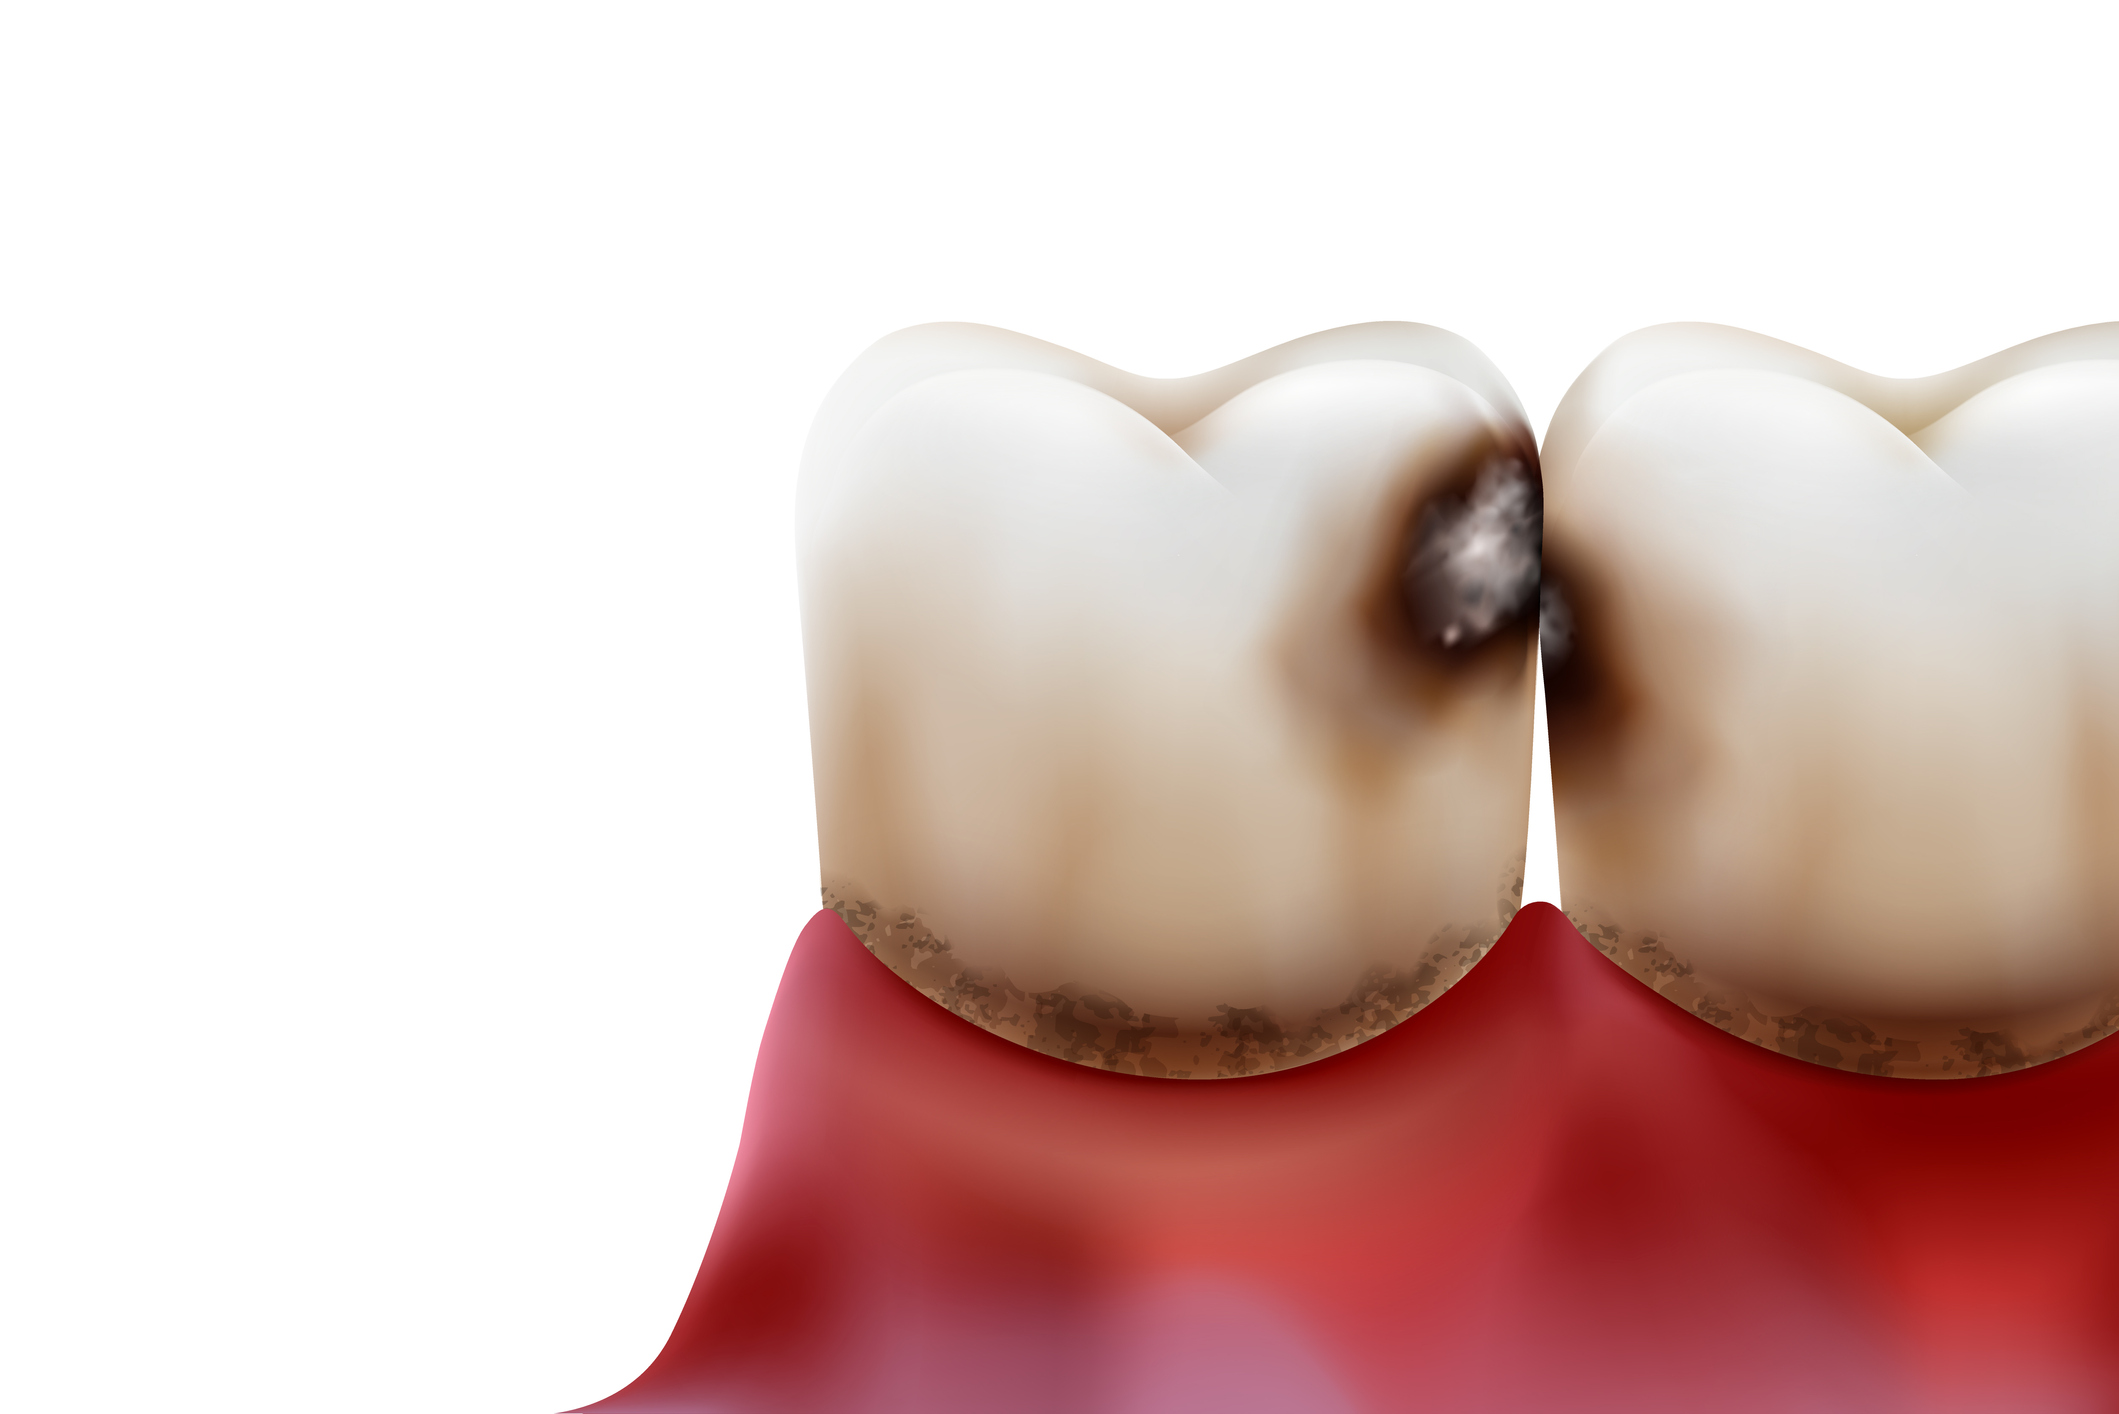

- Karies & Speichel Nur wenn man die Entstehung der Karies komplett verstanden hat, kann man sie effektiv verhindern und Ernährungs- und Zahnpflegeroutinen entsprechend anpassen. Interessant ist außerdem, dass es eine Art Wundermittel gegen Karies gibt: Den Speichel. Leider ist gerade unter geriatrischen Patienten Mundtrockenheit ein großes Problem mit teilweise gravierenden Folgen für Zähne und den Allgemeinzustand. Dem entgegenzuwirken ist also von großer Bedeutung.

- Zahnärztliche Auffälligkeiten Die Fähigkeit konkrete Probleme im Mund-Kiefer-Gesichtsbereich identifizieren und einschätzen zu können, bringt weitreichende Vorteile und teilweise entscheidende Konsequenzen mit sich. So ist es sinnvoll als Pflegefachkraft Kenntnisse über die Durchführung einer kurzen Untersuchung zu erlangen und die häufigsten zahnärztlichen Auffälligkeiten rechtzeitig erkennen zu können.

- Karies & Speichel Nur wenn man die Entstehung der Karies komplett verstanden hat, kann man sie effektiv verhindern und Ernährungs- und Zahnpflegeroutinen entsprechend anpassen. Interessant ist außerdem, dass es eine Art Wundermittel gegen Karies gibt: Den Speichel. Leider ist gerade unter geriatrischen Patienten Mundtrockenheit ein großes Problem mit teilweise gravierenden Folgen für Zähne und den Allgemeinzustand. Dem entgegenzuwirken ist also von großer Bedeutung.

- Zahnärztliche Auffälligkeiten Die Fähigkeit konkrete Probleme im Mund-Kiefer-Gesichtsbereich identifizieren und einschätzen zu können, bringt weitreichende Vorteile und teilweise entscheidende Konsequenzen mit sich. So ist es sinnvoll als Pflegefachkraft Kenntnisse über die Durchführung einer kurzen Untersuchung zu erlangen und die häufigsten zahnärztlichen Auffälligkeiten rechtzeitig erkennen zu können.